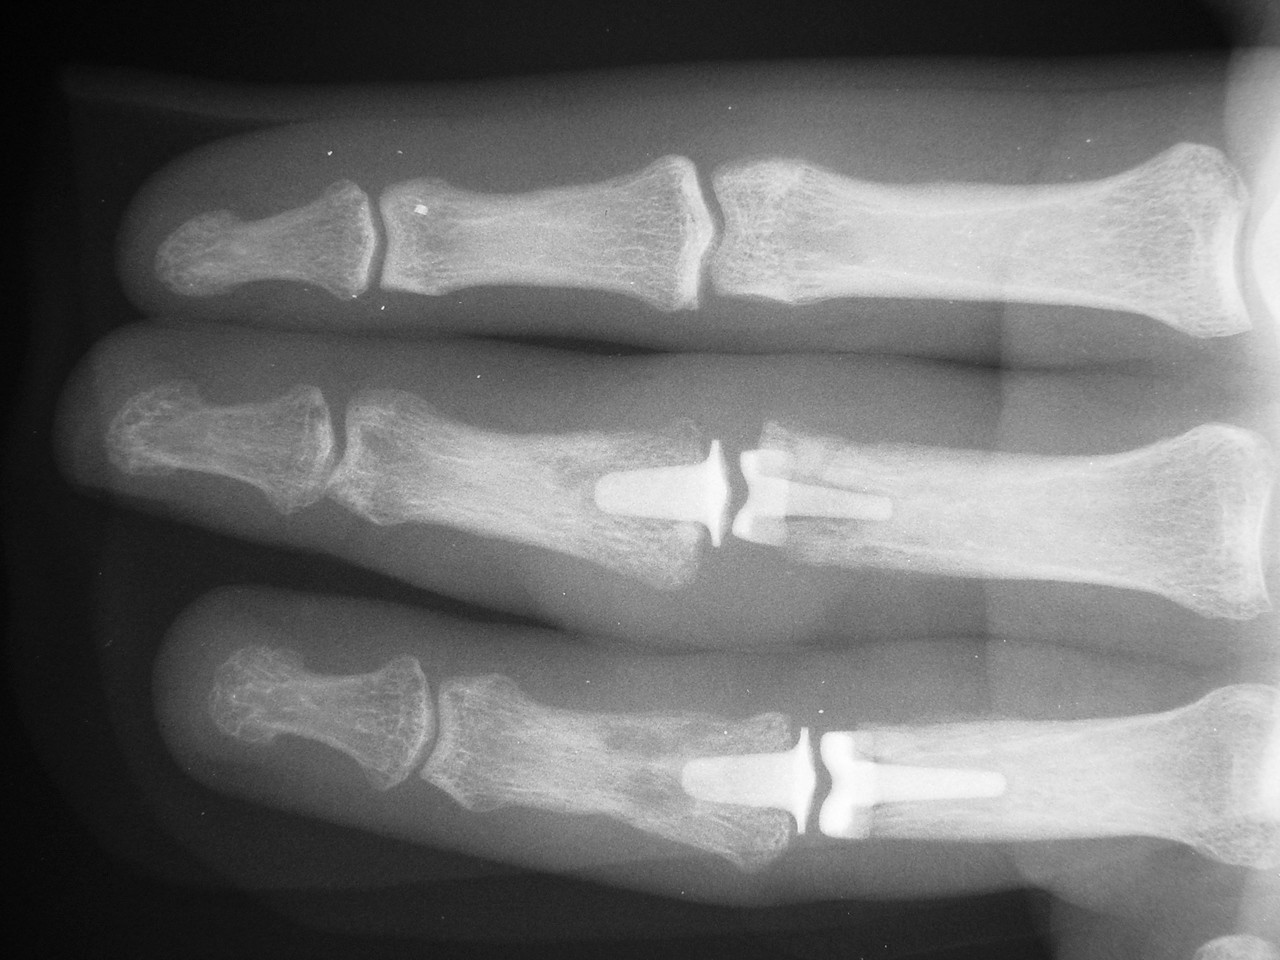

These are before and after radiographs of middle and ring proximal interphalangeal joints in a young man after a rotating blade injury resulting in dorsal bone and soft tissue loss. Initially treated elsewhere with K wire fixation, ring finger skin graft and abdominal flap reconstruction of the middle finger, he presented with instability, stiffness, pain and lateral angulation. Surgery was technically difficult because normal landmarks were distorted or missig. Despite complex bone and soft tissue loss,  stability was rendered in part by the restoration of concentric joint surfaces.

Correction of lateral deviation.

Click for larger image